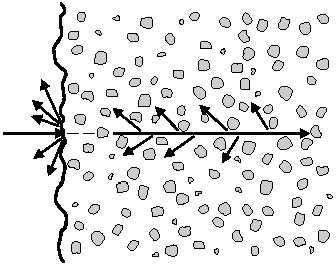

- Рассеивание — на границе органов и новообразований волны могут отражаться в неопределенных направлениях, что также способствует получению дифференцированного изображения.